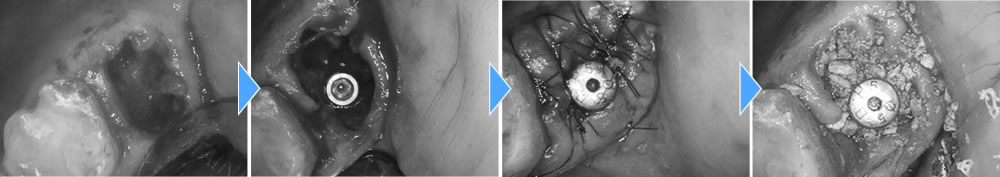

まず、保存が不可能な当該歯を抜き、中に溜まっている膿や感染物質を綺麗に取り除きました。次にインプラントを埋入し、無くなっている場所に骨を作る処置までを1度に行いました。